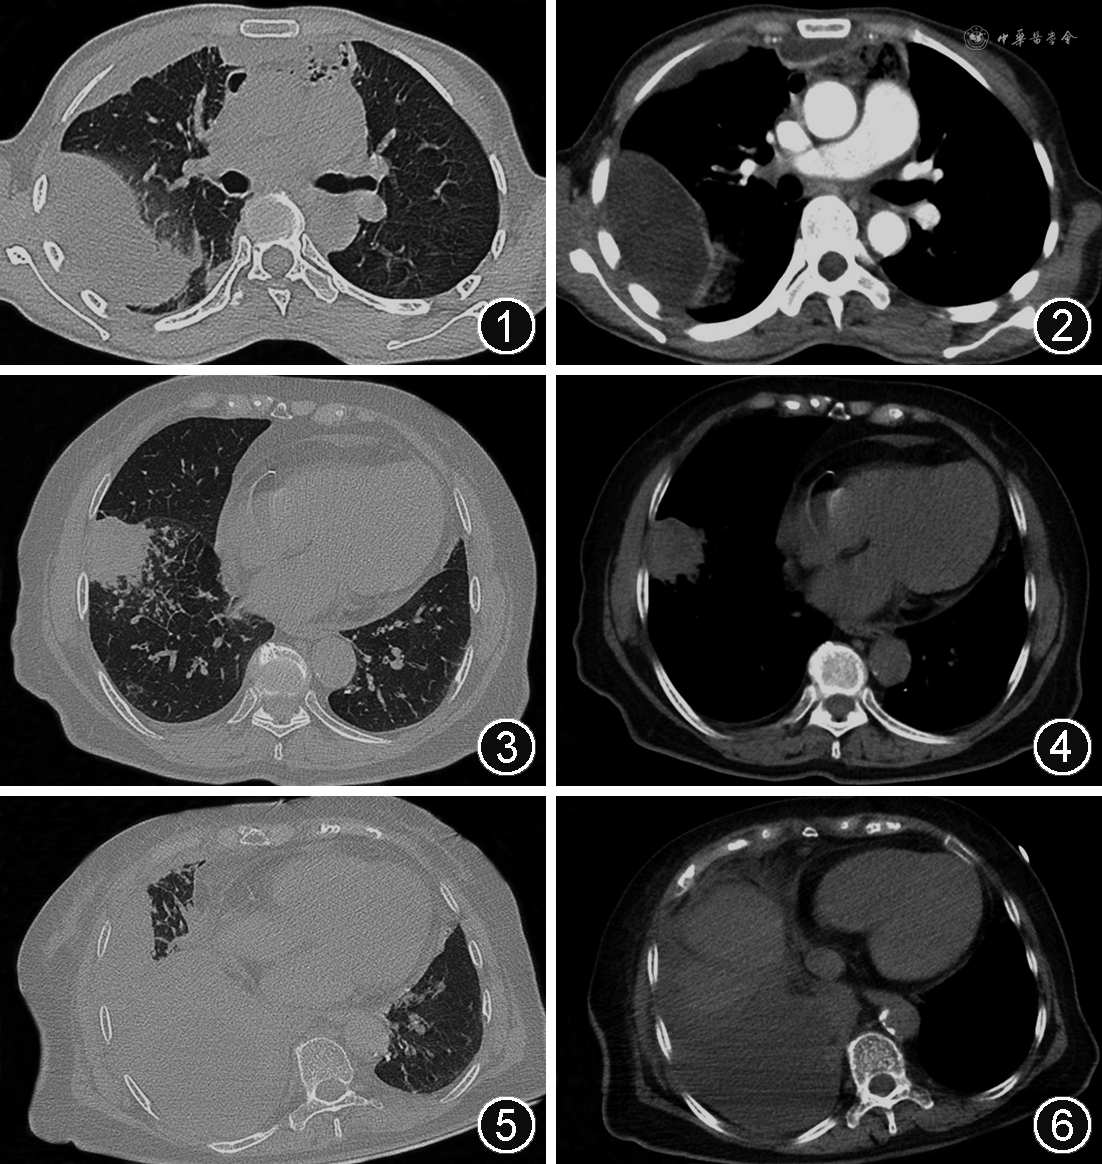

结果 患者的一般情况和临床表现见表1。合并慢性基础疾病的患者中,糖尿病14例,胃肠道肿瘤(术后)8例,慢性阻塞性肺疾病4例,支气管扩张症3例,肺癌(术后)2例,肝癌(术后)1例,银屑病1例。无慢性疾病患者中,2例有牙周炎病史,2例因食道异物导致食管胸膜瘘。44例患者符合脓胸诊断标准,2例胸腔积液及血培养均为星座链球菌。47例胸部CT表现为单侧胸腔积液,32例为包裹性胸腔积液,8例合并纵隔脓肿。2例牙周炎患者出现为颌面部、颈部及纵隔脓肿(图1,2)。1例患者为星座链球菌合并咽峡炎链球菌感染。12例患者合并其他病原菌感染,依次为大肠杆菌(3例)、阴沟肠杆菌(2例)、产气肠杆菌(1例)、肺炎克雷伯菌(1例)、表皮葡菌球菌(1例)、金黄色葡萄球菌(1例)、草绿色链球菌(1例)、念珠菌(1例)、啮蚀艾肯菌(1例)。所有患者均行抗感染治疗,45例行胸管引流,5例患者行手术清创引流。7例因呼吸衰竭行气管插管及机械通气。死亡患者中,4例为恶性肿瘤术后,1例为糖尿病(图3~6)。与非慢性疾病组患者相比,伴有慢性基础疾病组发病年龄较小,住院时间及抗感染治疗时间更长,但咳痰、胸痛发生率较低(均P<0.05),见表1。星座链球菌对克林霉素、阿奇霉素和红霉素的敏感性高于咽峡炎链球菌(均P<0.05),见表2。混合感染组和非混合感染组的临床分析见表3。